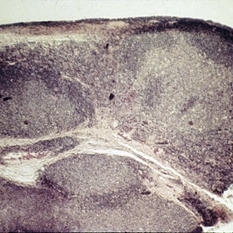

Noncaseating granuloma of the conjunctiva in a case of sarcoidosis.

Condition/keywords: conjunctiva, granuloma, sarcoidosis